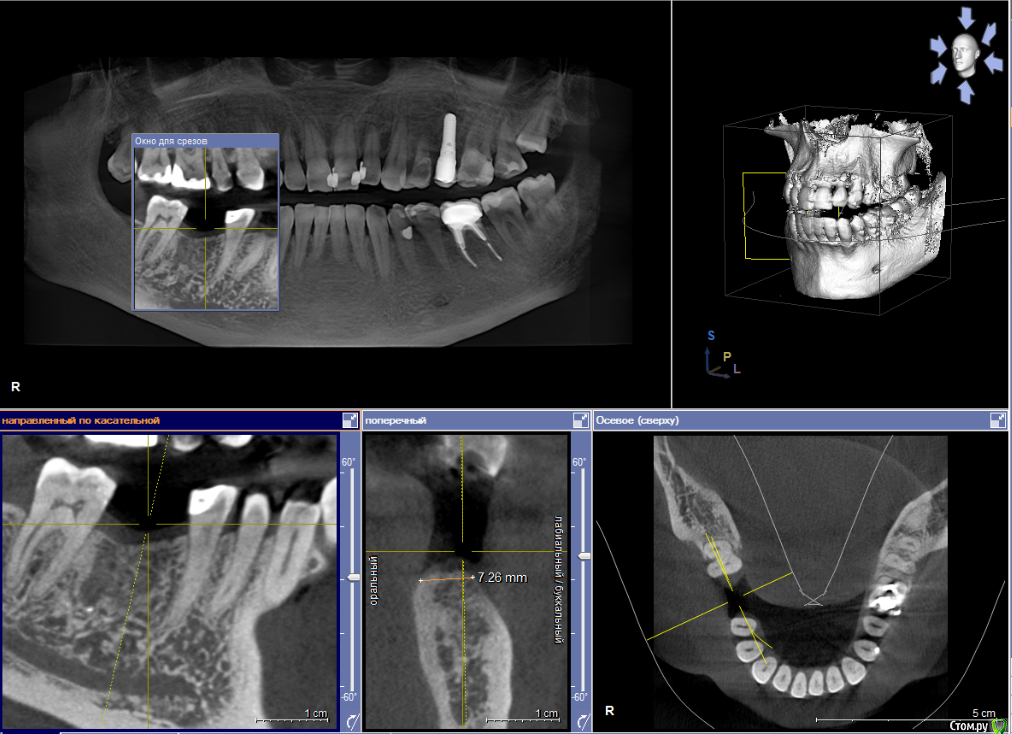

Dmitry DK Опубликовано 29 августа, 2019 Поделиться Опубликовано 29 августа, 2019 Добрый день всем! Случай достаточно заурядный, но возможно кому-то будет интересно. Результат - 2 года спустя 13 Ссылка на комментарий

Dmitry DK Опубликовано 18 сентября, 2019 Автор Поделиться Опубликовано 18 сентября, 2019 Да.Снимок скину На титановом основании сделано?Снимка нет с ортопедической работой? Ссылка на комментарий

Dmitry DK Опубликовано 18 сентября, 2019 Автор Поделиться Опубликовано 18 сентября, 2019 какая фиксация?Винтовая 1 Ссылка на комментарий